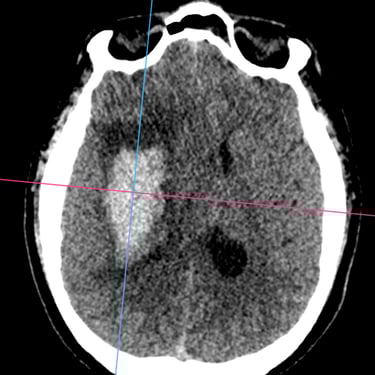

Hemorragia Intracerebral: Craneotomía y Evacuación del Hematoma

La hemorragia intracerebral es una emergencia neurológica grave que requiere diagnóstico rápido y tratamiento oportuno. Cuando el hematoma produce efecto de masa, deterioro del estado de conciencia o riesgo de herniación, la craneotomía y evacuación quirúrgica se convierten en la opción indicada. Este procedimiento permite abrir la bóveda craneal, retirar el coágulo y disminuir la presión intracraneal, preservando la función neurológica. Su objetivo es detener el daño secundario, mejorar la perfusión cerebral y estabilizar al paciente. La intervención temprana, combinada con cuidados críticos especializados, aumenta las posibilidades de supervivencia y recuperación funcional en este tipo de emergencia.